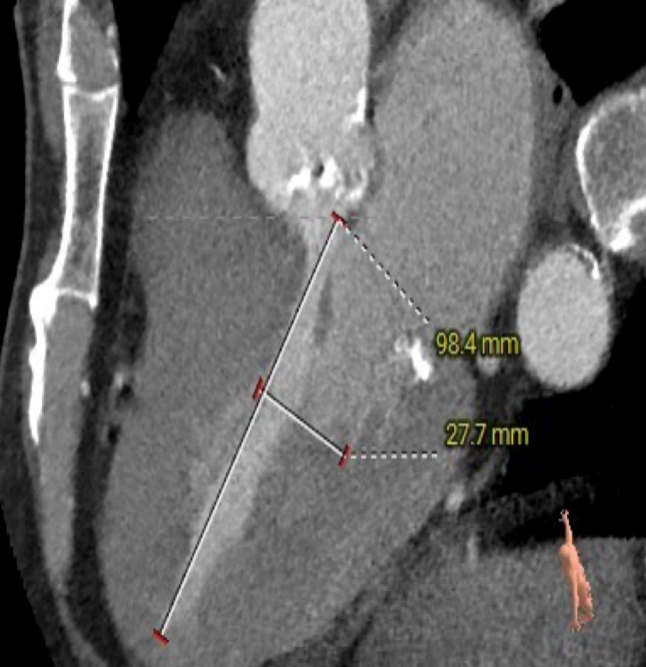

瓣环水平夹角

LEFT VENTRICLE

主动脉瓣瓣环周长66.2,平均周长径 21.1mm,SOV:32.2mm*36.4mm*34.1mm,瓣叶增厚,瓣上钙化分布不均,主动脉瓣环水平夹角67度,横位心。